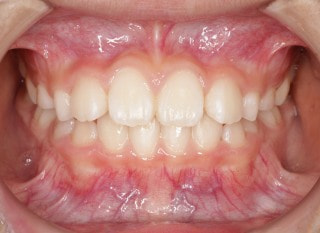

小児期第一段階

終了時